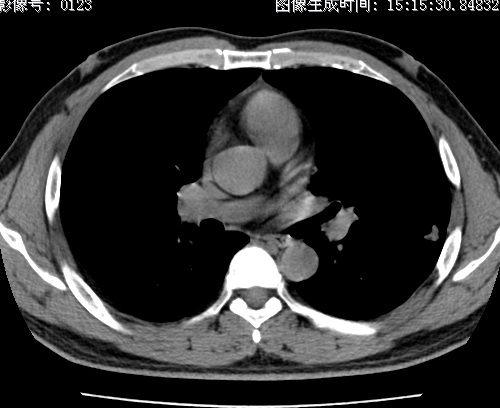

以下是引用zhao_bin2008在2010-1-4 20:15:00的发言:[br]先天性肺囊肿或小的肺隔离症?

以下是引用卜一在2010-1-4 22:09:00的发言:[br]先天性肺囊肿或小的肺隔离症?支持!

以下是引用zsl6918在2010-1-5 5:23:00的发言:[br]良性改变!肺囊肿,先天性支气管闭锁,血管畸形等均有可能。

以下是引用影像之路在2010-1-6 11:10:00的发言:[br]腺癌,最终的病检有些出乎意料之外,术前同志们大多考虑为肺囊肿或小的肺隔离征 [br]回过头来看 小结节呈分叶状,其内侧有一条较粗的静脉供血或许能成为支持诊断腺癌的理由